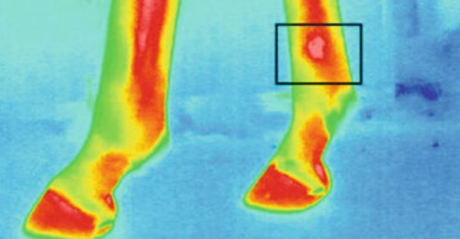

图为动物测温仪的马蹄热成像

屠宰前动物的压力水平对肉质至关重要。压力水平与动物的血液和体温相关。因此,重要的是监视并应对例如温度升高的温度。在运输过程中,测量猪耳朵的温度,发现温度与皮质醇的浓度和肌酸激酶的活性呈正相关。例如,诊断马匹的行走时,动物测温仪热成像会很有用。建议使用热成像来检测炎症和其他异常情况,特别是在马的腿和蹄中。并且也已经进行了对诸如蛙等外热动物的热力学特性的分析。测量了从8℃(人工冬眠)到23℃(人工唤醒)加热过程中青蛙不同身体部位的温度。在这样的实验中,动物测温仪进行测量而不会伤害或接触动物是一个很大的优势。